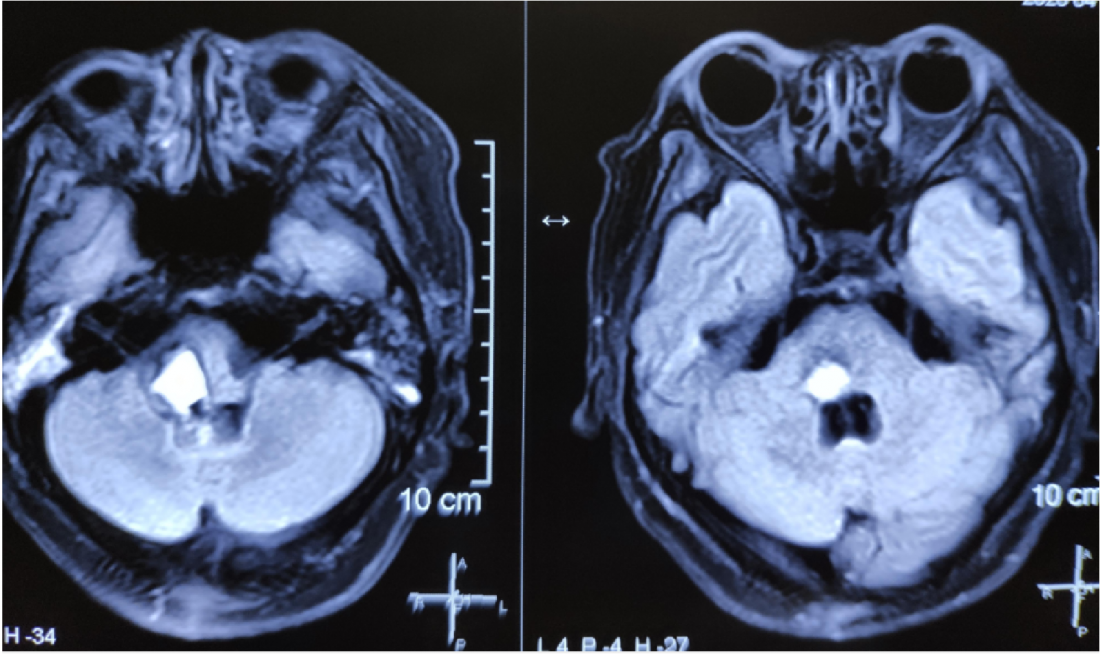

患者李某银,女,56岁。因“头晕,口角歪斜伴左侧肢体麻木乏力2月”入院,以无明显诱因头晕伴左侧面部口角歪斜,并左侧肢体麻木乏力为主要表现,于外院行脑MR增强提示脑干占位性病变,血管母细胞瘤可能性大。

MR显示桥脑右侧高信号影,肿瘤位于四脑室界沟上方之桥脑部分,邻近面丘及动眼神经核,因此患者出现面瘫。

肿瘤位于桥脑与延髓交界处

面神经丘受压明显

术后MR:

术后患者病理为血管网质细胞瘤。患者恢复良好,行走如常KPS评分90分出院。原先口角歪斜纹明显改善,肢体麻木明显减轻。